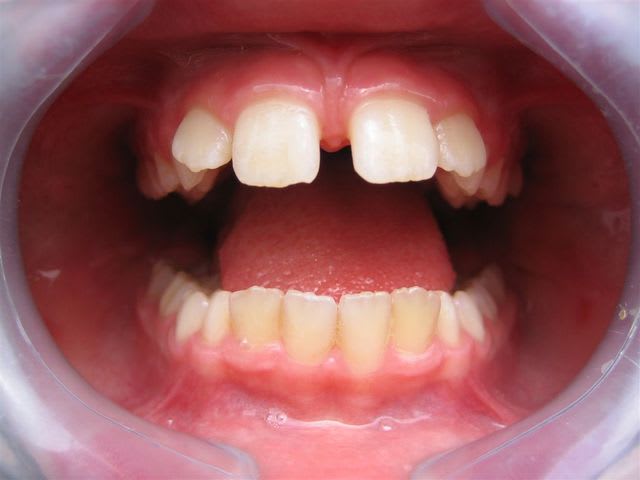

C’est un cas simple ou il faut juste stimuler un peu la croissance et reformer les arcades.

C’est le type même du traitement d’interception en denture mixte.

Pas de panique, petite DDM, bonne classe 2 sq,un peu de supracclusion ---> la laisser grandir un peu, et la confier à un ODF pour un peu de fonctionnelle et un alignement.

... elle est en classe I, avec une grosse supra.

TT "fonctionnel" prévu dans qqs semaines.

... c'est en cours ... un appareil de chez Rocky Mountain va être mis en place, à porter environ 16 heures/jour; il va falloir que je m'en fasse expliquer le principe lors de la séance de pose.